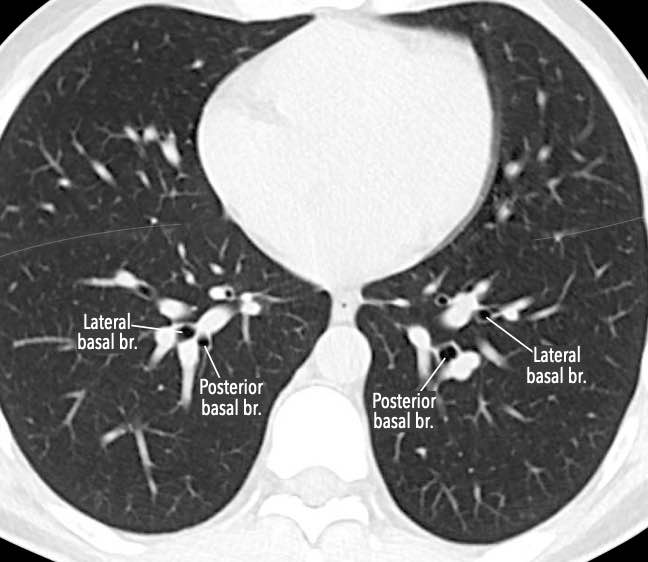

Phế quản trên CT

Cuộn qua các hình ảnh để quan sát khí quản phân chia thành phế quản chính phải và trái, sau đó tiếp tục phân chia thành các phế quản thùy và phế quản phân thùy.

Các phân thùy phổi trên CT

Cuộn qua các hình ảnh để quan sát cách phổi được phân chia thành các phân thùy.